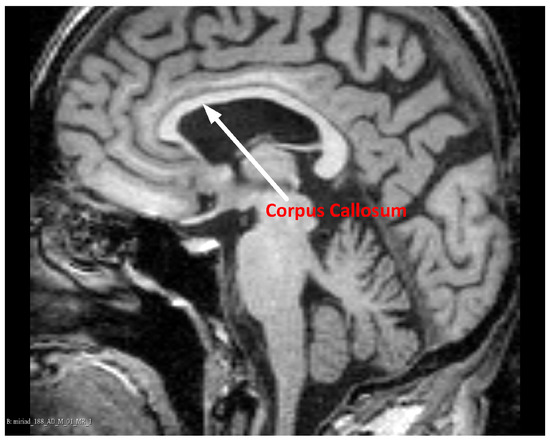

Magnetic Resonance Imaging (MRI) ensures high contrast between various soft tissues, so it is the preferred method of examining the brain, including the CC. In T1-weighted MR images of the brain, acquired in the sagittal plane, the CC has a curved, elongated shape of the inverted letter C, with a high intensity of pixels. An example CC image in the sagittal plane is shown in Figure 1.

Figure 1. The Corpus Callosum (CC) in an example midsagittal brain Magnetic Resonance (MR) image. Data source: Minimal Interval Resonance Imaging in Alzheimer’s Disease (MIRIAD) [11], from the ’miriad_188_1_MR_1’ set.